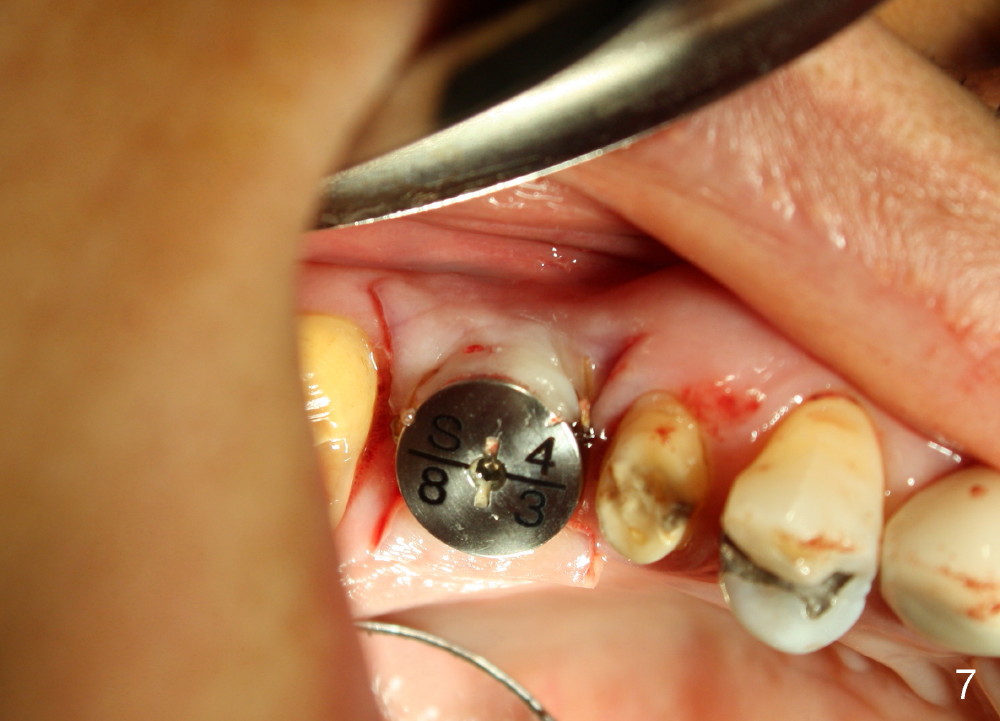

The bone density (Fig.1 white *) at the edentulous area (#3) is lower than that at the dentulous one (black *, 50 year-old man). The buccal plate is also atrophic and concave (Fig.2,3 arrowheads). A series of bone expanders are used to form osteotomy (following 1.6 mm pilot drill) at the depth of 14 mm (Fig.3 E 3.0 mm in diameter). When the last expander (4.3 mm) is removed from the osteotomy, the buccal plate appears to have been moved buccally (Fig.5 arrowheads). A 5.3x14 mm submerged implant (Fig.6 I) is placed with insertion torque >35 Ncm. The buccal plate seems to improve following placement of an 8.2 mm healing abutment and suturing (Fig.7). No bone graft is used. The buccal plate remains normal 12 days postop (Fig.8). It is slightly concave 3 months postop (Fig.9) with minimal bone resorption at the crest (Fig.10 (H: healing abutment),11 (A: cemented abutment). Nine months post cementation (12 months postop), bone resorption at the crest remains minimal (Fig.12) while the buccal plate (Fig.13 *) at #3 remains strong. Bone loss appears not to get worse 22 months post cementation (Fig.14). Soft and hard tissues remain healthy around the implant crown 3 years (Fig.15) and 3.5 years (Fig.16,17) post cementation.